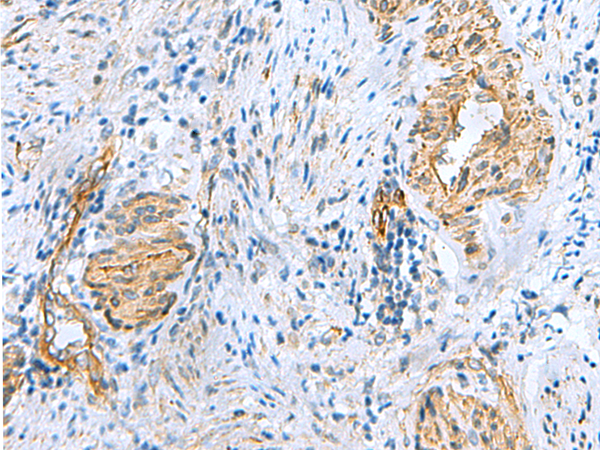

分类: 科研抗体货号: P03307别名: ATPO; OSCP; ATP5O; HMC08D05应用: WB,IHC反应种属: Human, Mouse